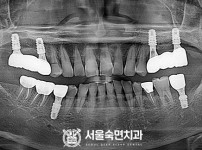

상악동거상술, 뼈이식 / 숙면임플란트 13개 - 오스템임플란트 (이*웅님)

해당 게시물은 의료법 제56조에 의거하여 로그인 후 열람이 가능합니다.

구분 임플란트